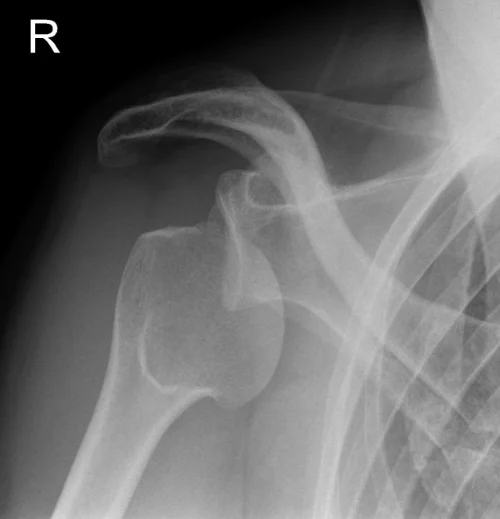

Jasnit Makkar claims to be amazing on the court. Unfortunately during each of our one on one match ups - he has suffered a shoulder dislocation, rendering him unable to complete a game. I question the validity of his injuries, as they always seem to occur towards the end of a game when the opponent has lead. In any event, if we took an xray of his shoulder, this is what it would have looked like. Unfortunately shoulder dislocation often lead to labrum tears which often require season ending surgery such as in the case of Kevin Love during last seasons playoff run.

Here, you can see the humeral head (ball looking thing on left) is not up against the glenoid or scapula. The two should fit together like a puzzle.